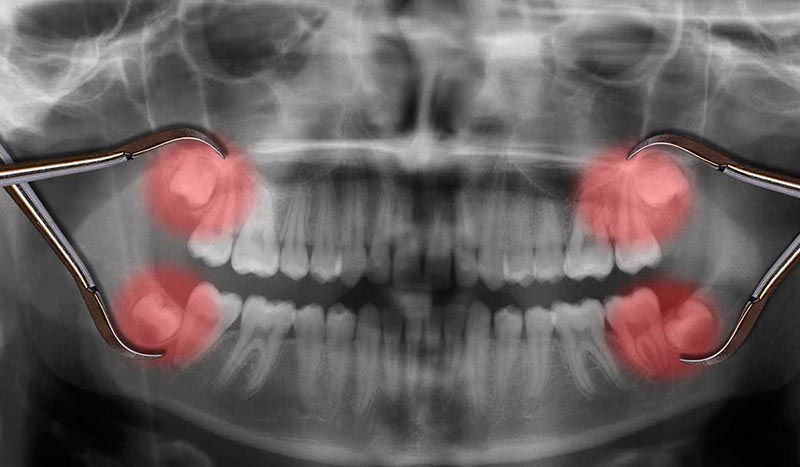

Our permanent teeth are meant to last a lifetime with us. However, there are also reasons for them to be extracted. Some of these reasons can be more common than others, such as the extraction of wisdom teeth. While others can be more problem based:

- Wisdom tooth surgery (simple) : 60 Euros